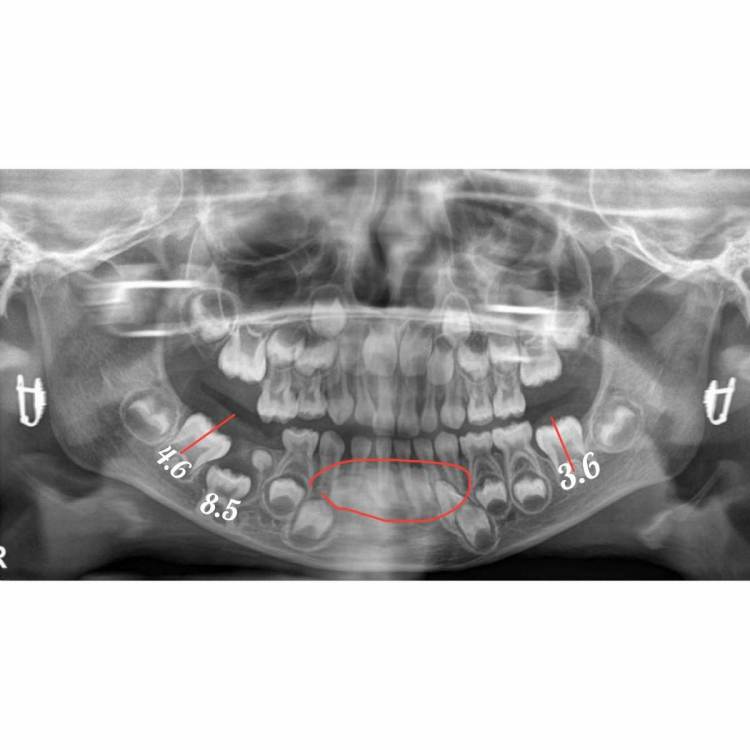

CRAZYDUCK Опубликовано 21 июня, 2022 Поделиться Опубликовано 21 июня, 2022 Направить на кт этой зоны ( визуализировать «образование», понять с чем имеете дело , двухмерного снимка недостаточно . удалять 8.5 однозначно , это анкилоз . Удаление в условиях общего обезболивания ( наркоз ). 8.5 анкилозирован, в таком случае этот зуб не даёт нормально развиваться участку челюсти . Это уже видно на снимке - обратите внимание на продольную ось 4.6 , она наклоняется в сторону анкилоза . Сравните с нормальной стороной 3.6 зуб . Удалить в плановом порядке , из-за сложности предстоящего удаления - челюстной лицевой хирург , работающий с детьми . 1 1 Ссылка на комментарий

CRAZYDUCK Опубликовано 21 июня, 2022 Поделиться Опубликовано 21 июня, 2022 После восстановления понадобится помощь врача ортодонта , профилактика смещения зуба 4.6 вперёд . зону нижних передних зубов тоже наблюдать ( обвела красным ) у ортодонта я думала вопрос задаёт врач . Поэтому отвечала таким языком . Сейчас нарисую на вашем снимке для наглядности 1 1 Ссылка на комментарий